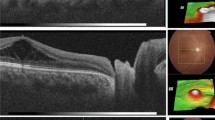

To evaluate surgical intervention with pars plana vitrectomy (PPV) for correction of optic disc pit maculopathy (ODP-M).

Retrospective chart review from 13 centres of 51 eyes of 50 patients with ODP-M who underwent PPV between 2002–2014. Anatomic and final best-corrected visual acuity (BCVA) outcomes were evaluated for all cases with different adjuvant techniques.

There were 23 males and 27 females with median age 25.5 (6–68) years. Preoperative median foveal thickness was 694.5 (331–1384) μm and improved to 252.5 (153–1405) μm. Median BCVA improved from 20/200 (20/20000 to 20/40) to 20/40 (20/2000 to 20/20) with 20/40 or better in 31 eyes. Complete retinal reattachment was achieved in 44 eyes (86.3%) at 7.1 (5.9) months. The good surgical outcomes were achieved in different adjuvant groups. Median follow-up was 24 (6 to 120) months.